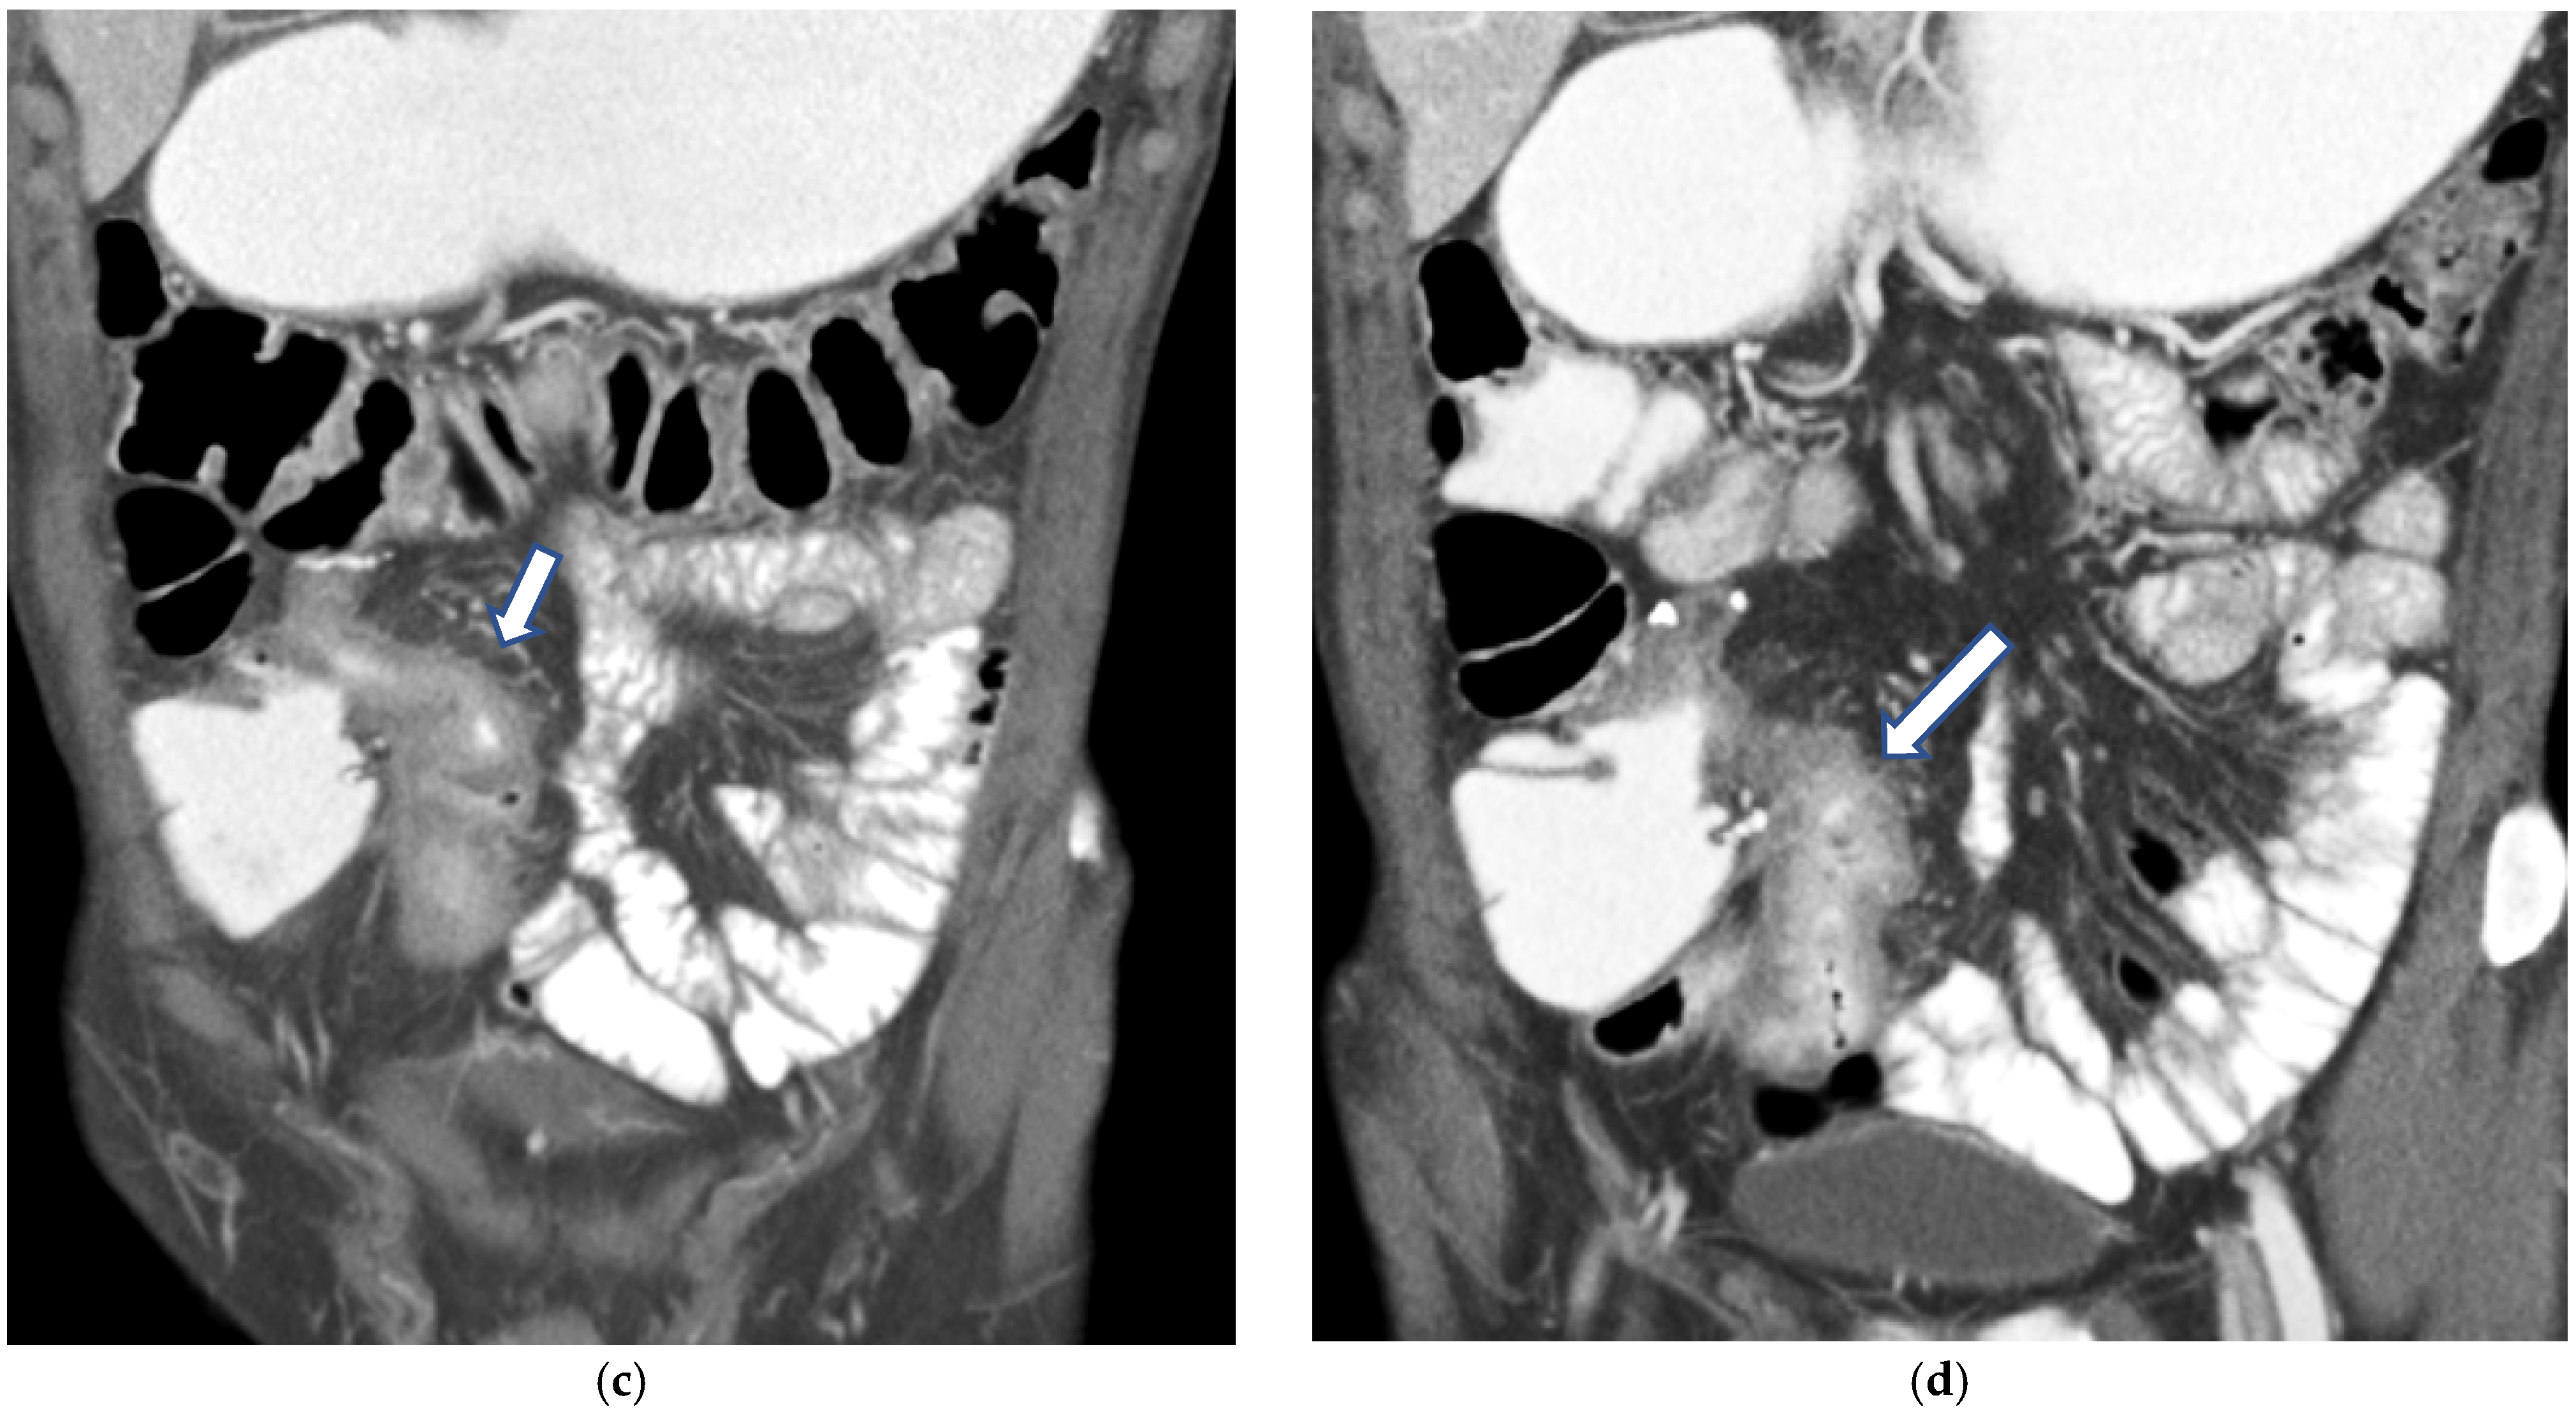

CT Enterography (CTE) is a dedicated technique that can be performed using either neutral (water macrogol solutions) or positive (iodinated) oral contrast for optimal luminal distention, thereby enhancing the modality’s utility in elective outpatient evaluation, shown on Figure 4 and Figure 5. CTE performed with positive oral contrast improves visualization of the entire small bowel lumen and interloop relationships, and is particularly useful in complex disease associated with adhesions and fistulas (Figure 4a–d and Figure 5a–d). On the other hand, CTE performed with negative oral contrast enables assessment of mucosal hyper-enhancement, wall thickening, and inflammatory changes (Figure 5). However, although CTE can approximate much of the mural and extramural information obtained with MRE, it lacks the functional imaging capabilities of MRI and cannot distinguish with confidence between inflammatory and fibrotic strictures. For this reason, CT is generally reserved for situations in which MRE is unavailable or contraindicated, or when specific luminal abnormalities, such as unexplained focal thickening or suspected small-bowel polyps, require rapid clarification [20,21,39,40,41].

Figure 4.

(a,b) Axial CT scan in the venous phase after administration of positive oral contrast medium (Gastrografin) showing thickened terminal ileum in a 65-year-old patient with Crohn’s disease. (c,d) Coronal CT scan in the venous phase after administration of positive oral contrast medium (Gastrografin) showing thickened terminal ileum (arrows) in a 65-year-old patient with Crohn’s disease.